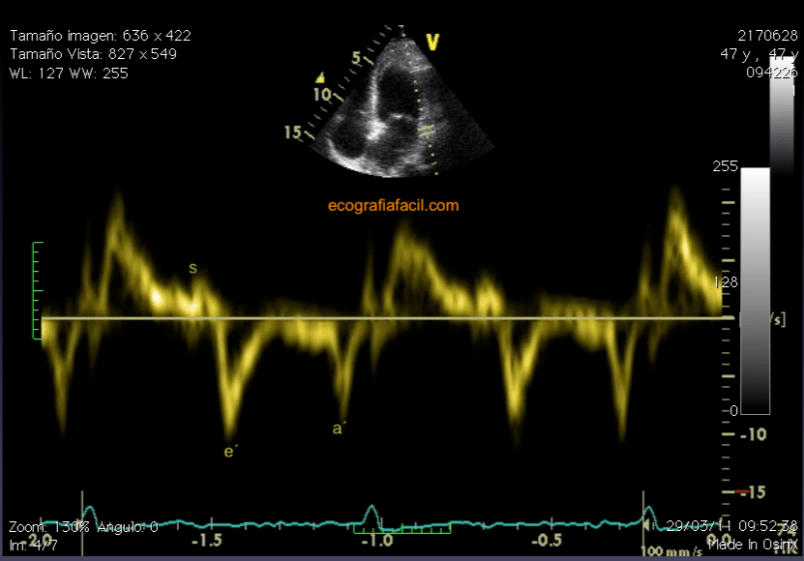

Una vez valorado el flujo transmitral, vamos a por un Doppler tisular espectral en el anillo lateral mitral (figura 19). La relación que encontremos entre los valores de la onda E (sangre) y la onda e´(anillo) me ayudará a establecer la función diastólica.

Once the transmitral flow is assessed, we go for a spectral tissue Doppler in the lateral mitral ring (Figure 19). The relationship that we find between the values of the wave E (blood) and the wave e'(ring) will help me to establish the diastolic function.